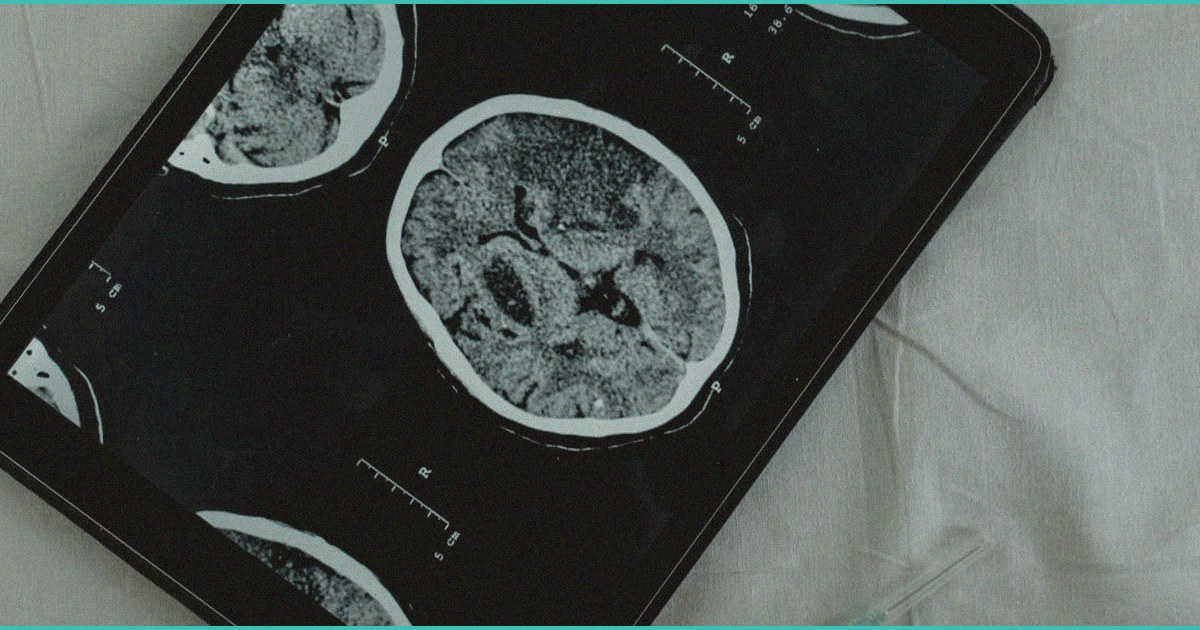

A recent large-scale study suggests that cannabis use in older adults may have neuroprotective benefits, challenging conventional assumptions about cannabis and cognitive aging. The research indicates potential mechanisms by which cannabinoids might support brain health in elderly populations, though the article does not specify which cognitive domains were examined or the magnitude of observed effects. For clinicians managing older patients, this finding adds nuance to risk-benefit discussions around cannabis, particularly for those with age-related neurodegeneration or cognitive concerns where traditional treatments have limited efficacy. However, the clinical applicability remains limited without clarity on dosing, cannabinoid ratios, and comparison to established neuroprotective interventions. Clinicians should exercise cautious optimism and await peer-reviewed publication details before incorporating cannabis into routine cognitive aging management, while remaining open to discussing this emerging evidence with informed patients seeking alternative or adjunctive therapies.

“What we’re seeing in the aging population is that low-dose cannabis, particularly THC-dominant formulations, may enhance neuroplasticity and reduce neuroinflammation in ways that actually support cognitive function rather than impair it, which contradicts decades of messaging about cannabis and the brain. The key distinction my patients need to understand is that this benefit appears specific to later life, modest dosing, and regular rather than acute use, and we still need prospective randomized trials before I’m recommending it as a preventive strategy. But the signal is real enough that I’m no longer dismissing it out of hand when a 70-year-old asks whether cannabis might help their memory.”

๐ง While preliminary findings suggesting cognitive benefits of cannabis in older adults are intriguing, clinicians should approach these claims with appropriate skepticism given the significant methodological limitations of observational studies in this space, including reverse causality, unmeasured confounding, and selection bias that could explain apparent associations. The existing literature on cannabis and cognitive aging remains mixed, with some studies documenting memory and processing speed declines while others report null or potentially beneficial effects, making it difficult to establish clear causal relationships. Additionally, older adults often use multiple medications and have varied comorbidities that could interact unpredictably with cannabinoids, and the heterogeneity of cannabis products in terms of THC/CBD ratios and administration routes further complicates any generalization of findings. Rather than recommending cannabis for cognitive aging based on current evidence, clinicians should continue assessing individual risk-benefit profiles in older patients who are already using cannabis, remain alert to